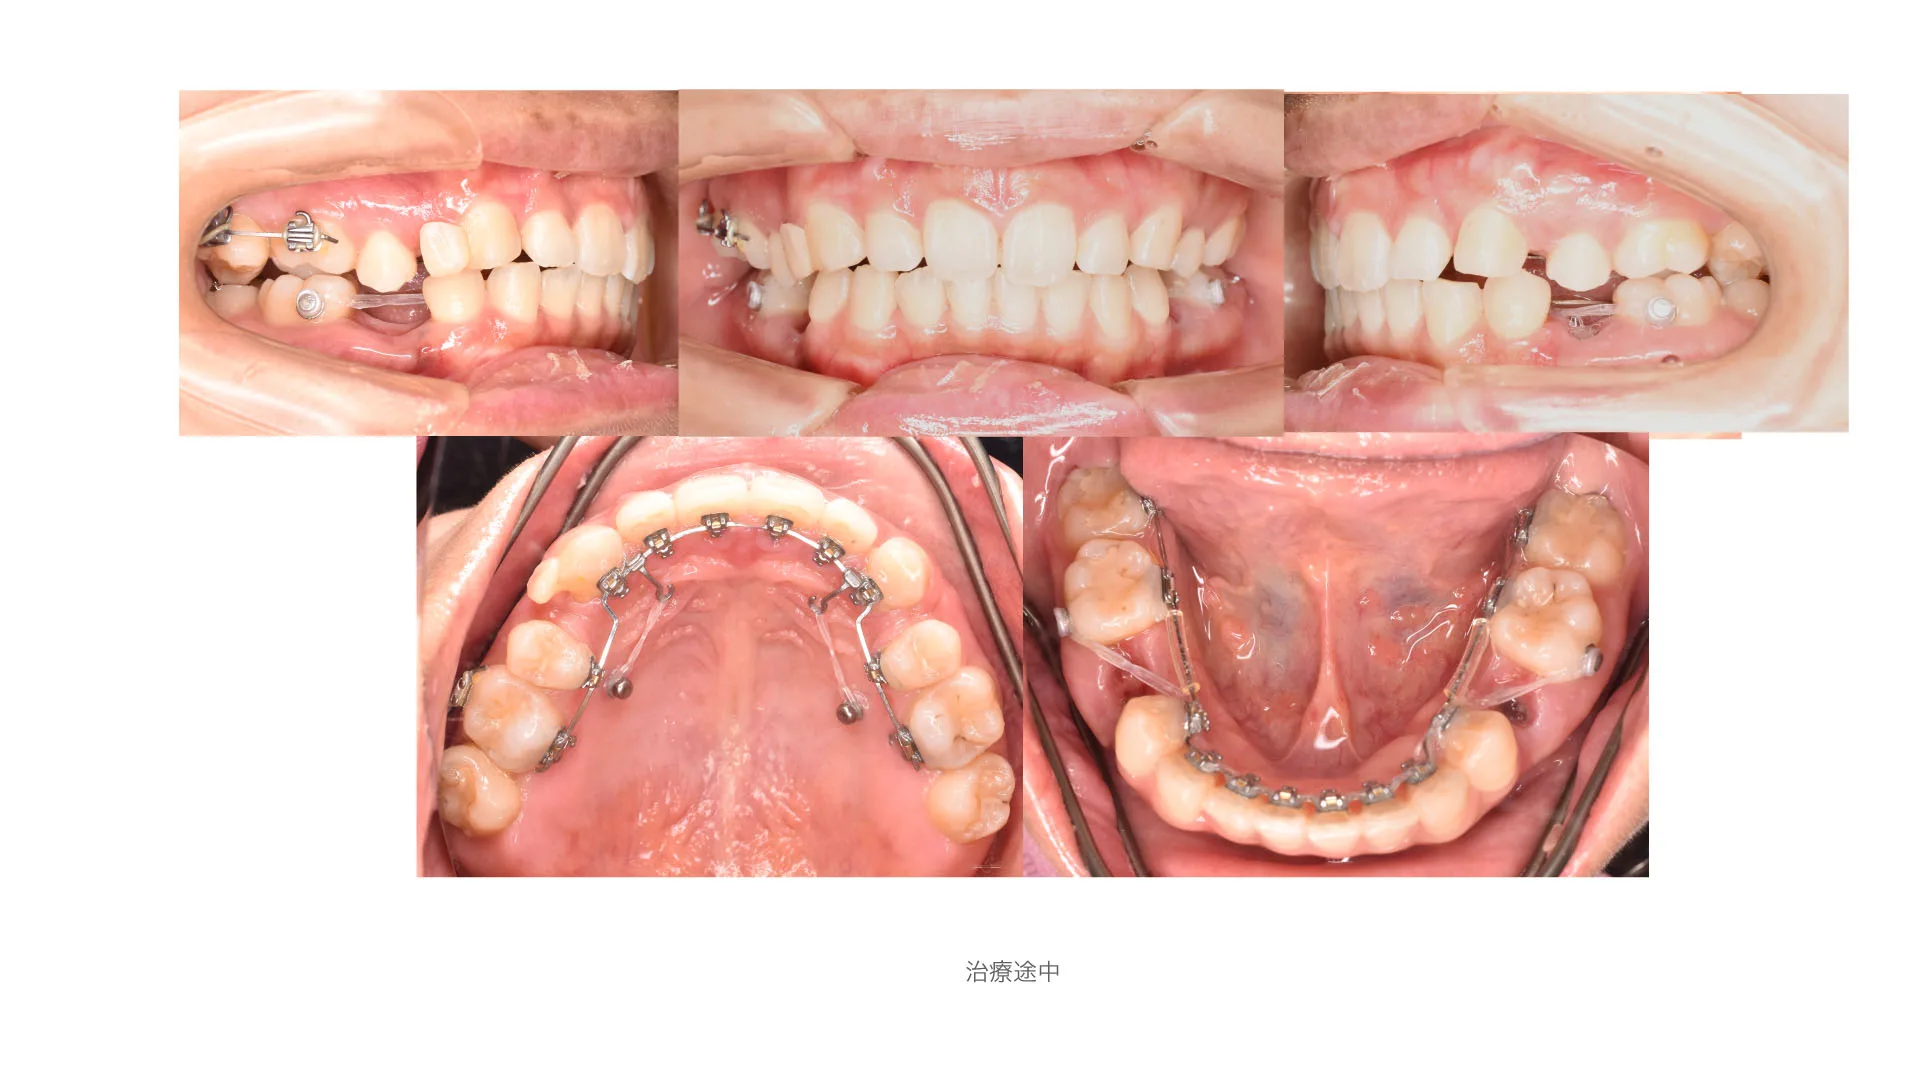

症例 口唇突出、正中離開